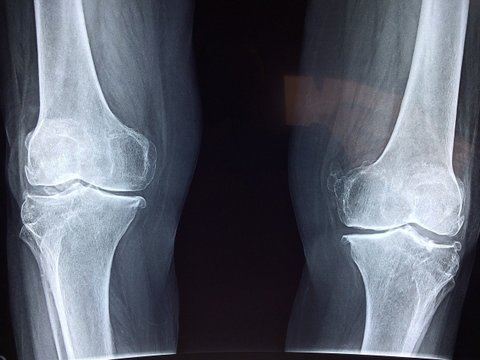

관절에 좋은 약초 모음